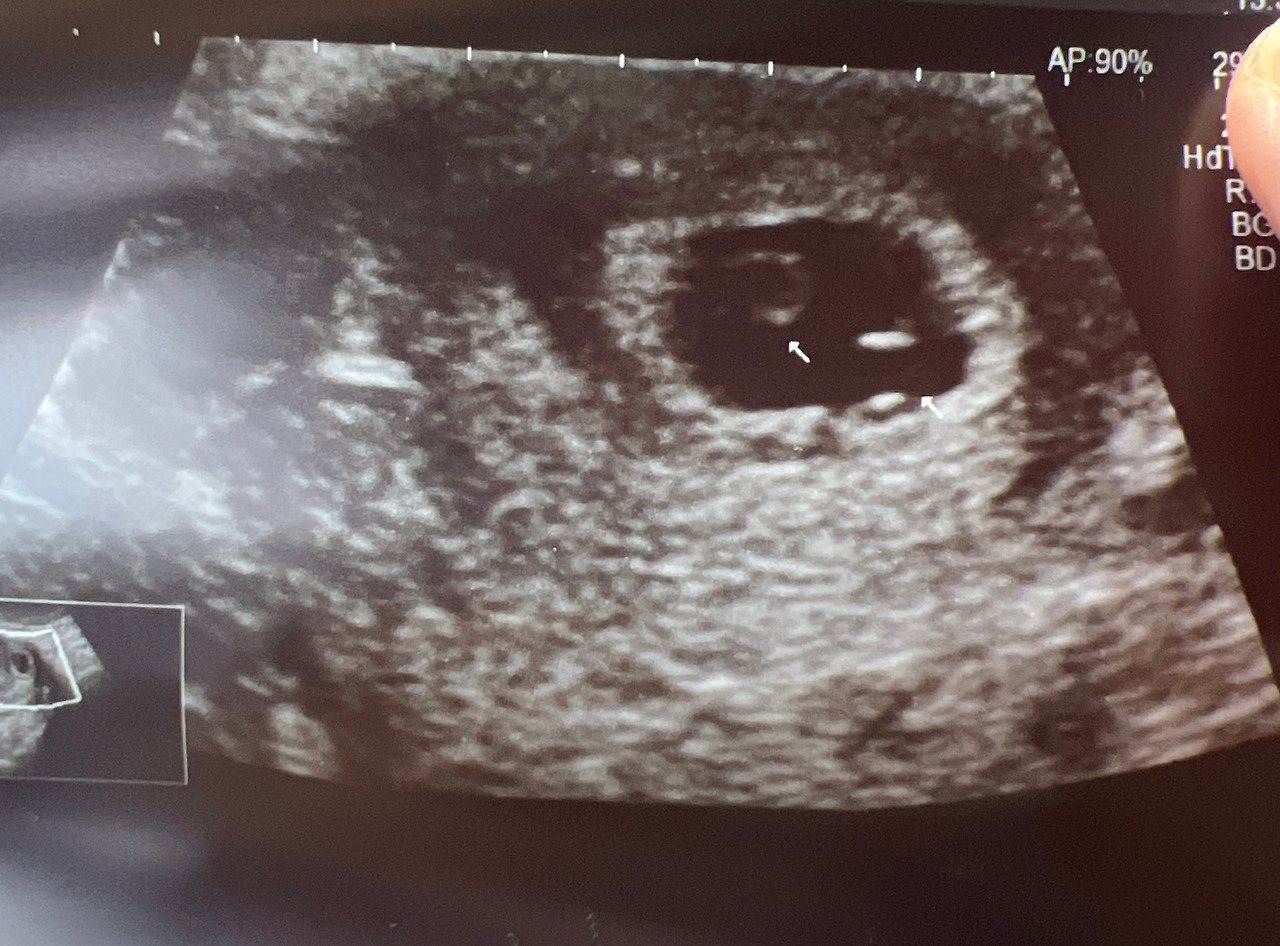

7주 차에 초음파를 보러 갔는데 선생님이 ‘혹시 집안에 쌍둥이가 있나요?’ 하셨다.

‘난황이 두 개 같아서요. 아기집은 하나라 일란성쌍둥이 가능성도 있을 것 같아요.’ 하신다.

‘아 아니네요. 분명 난황이 두 개였는데 지금은 하나예요.‘

우선 내게는 안정적인 게 가장 중요했기 때문에 쌍둥이가 아니라는 것에 안도했다. 아무리 생각해도 열매가 동생을 데려다준 것 같다. 그래서 난황 두 개를 보여주며 자기 잘 있다고 내가 데려다주는 거라고 알려준 거 아닐까? 기특한 우리 딸.